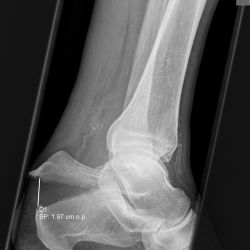

Entenschnabelfraktur